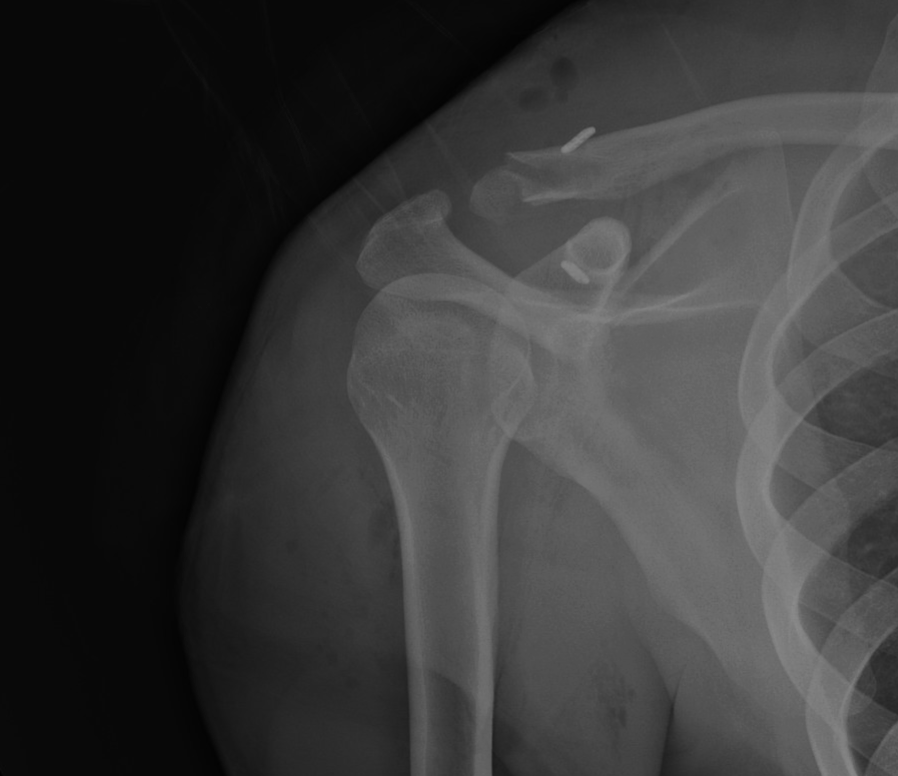

X-ray of a shoulder showing a broken clavicle, with magnetic metal pins placed to stabilize the fracture.